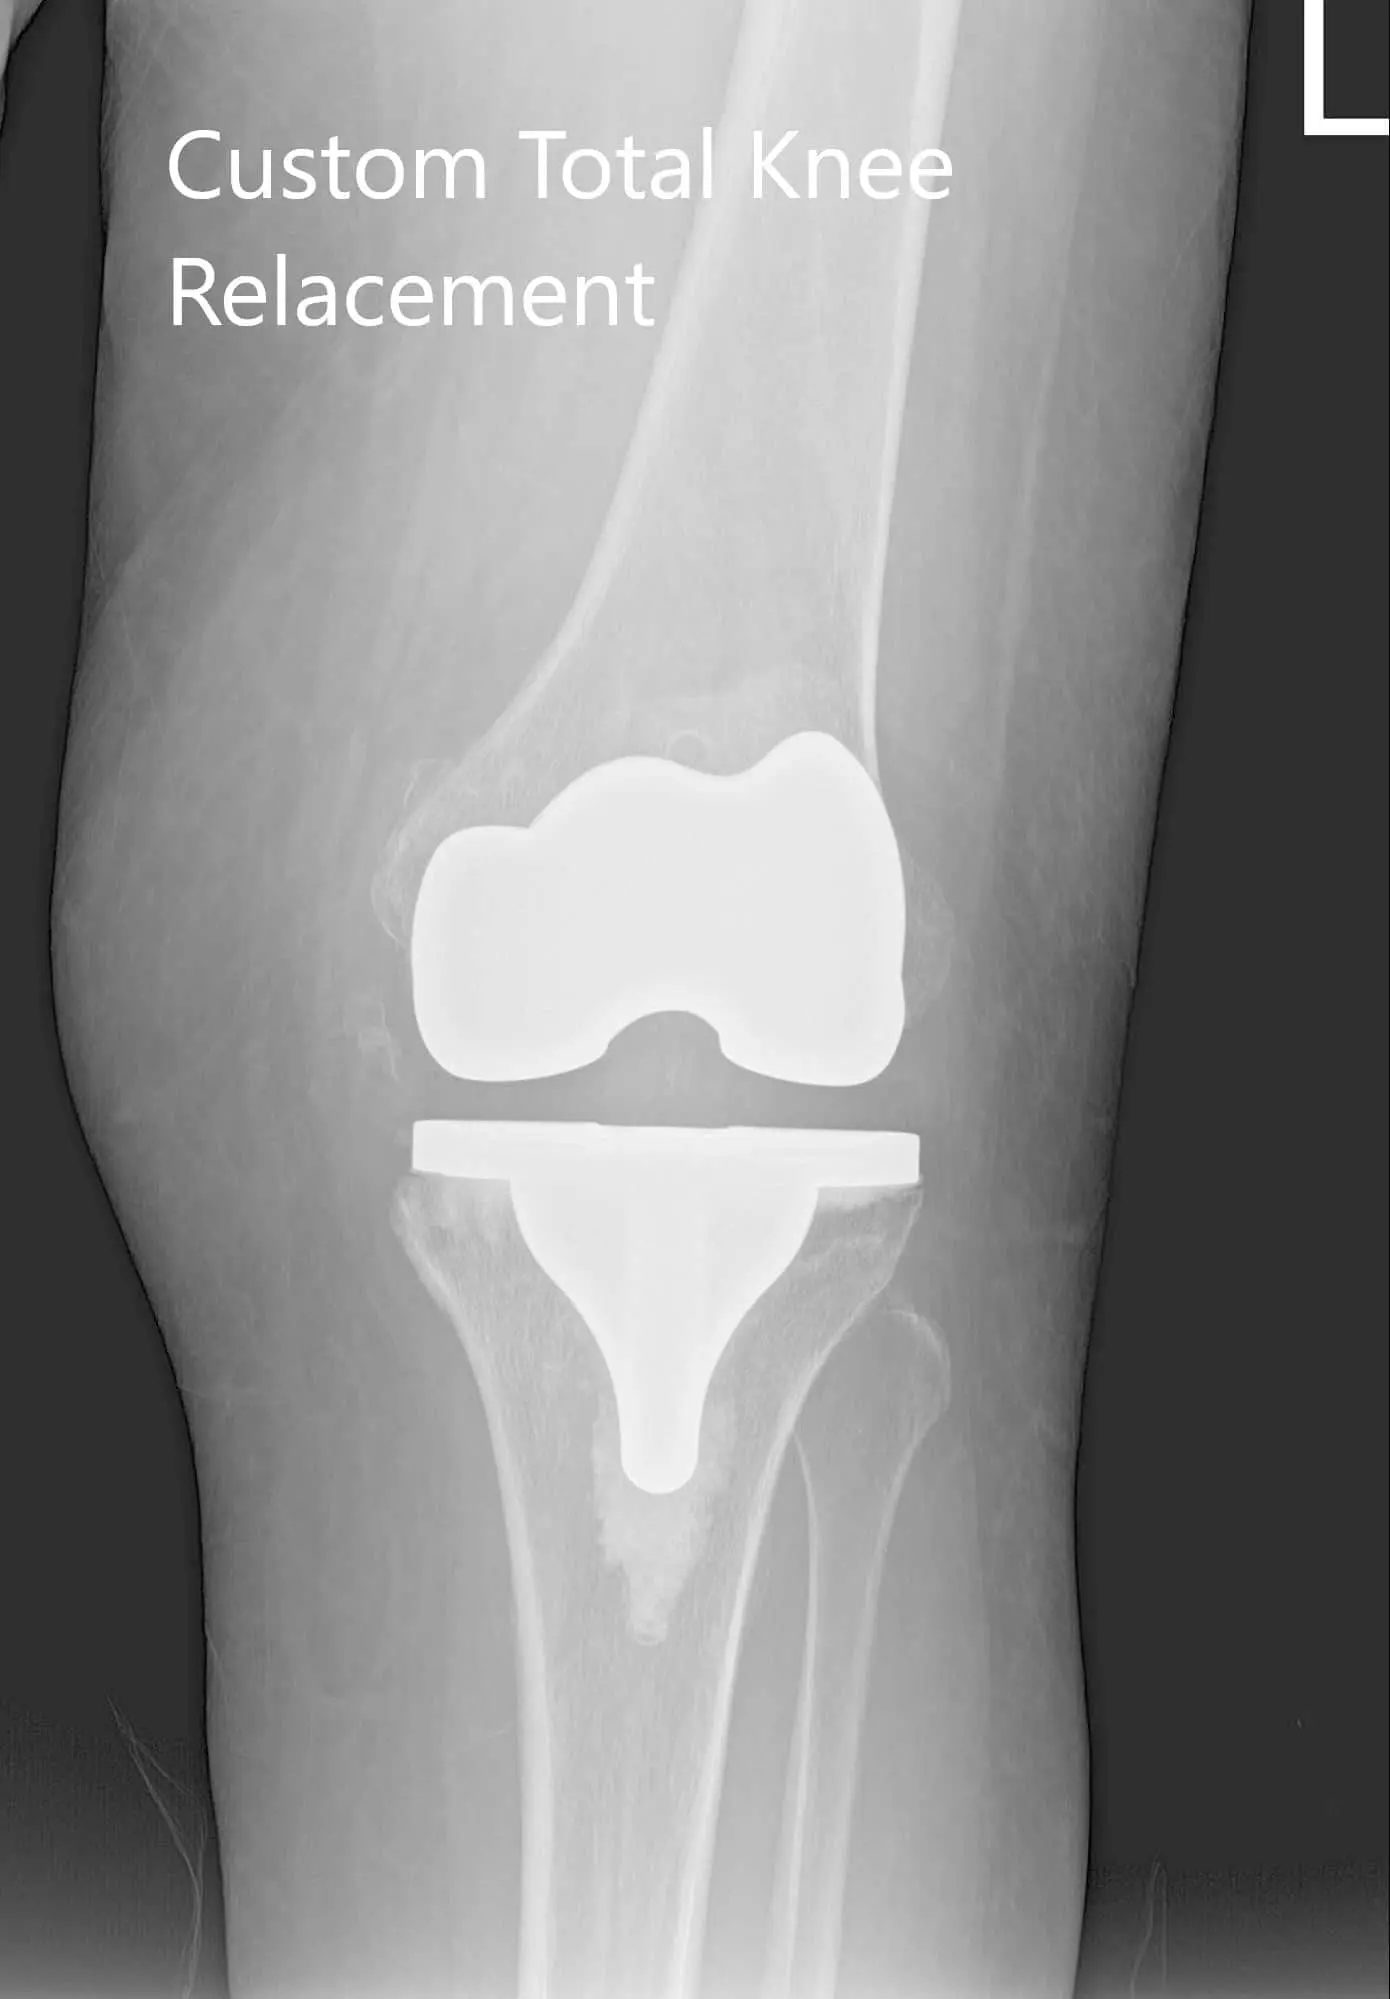

Postoperative X-ray showing AP and lateral views of the right and the left knee joint